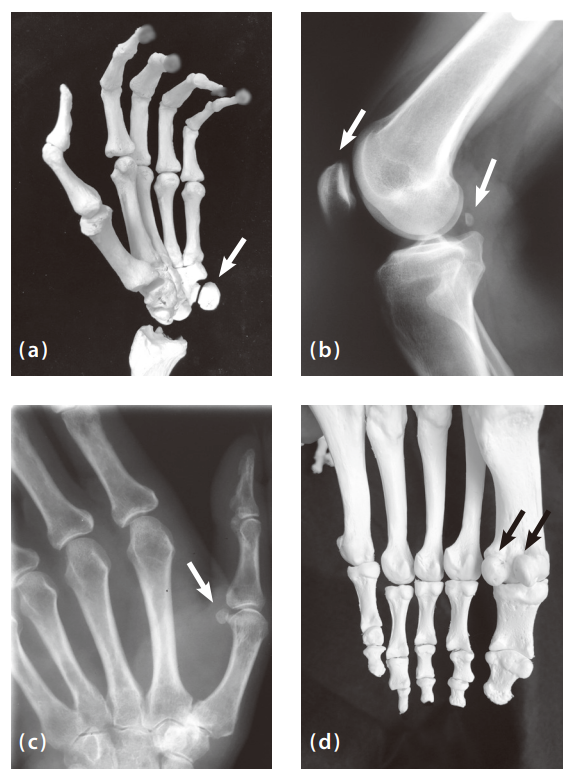

먼저, 세는 사람이 누구인가에 따라 다르다. 오랫동안 파묻혀 있던 화석에서 먼지를 털어내는 고생물학자는 몇 개의 미세한 뼈를 빠뜨릴 수 있다. 그가 상습적으로 빼먹는 것 중에는 종자뼈(sesamoid)라는 것이 있는데, 힘줄 속에 박혀 있는 작은 뼈로 전신의 관절과 인접한 곳에서 발견된다. 참깨(세서미)와 비슷하게 생겼다고 해서 영어로는 ‘세서모이드’라는 이름을 얻었으며(그러나 인간의 경우에는 참깨보다 크며, 케이퍼에 더 가깝다), 우리가 손으로 물체를 쥐거나 발로 체중을 떠받칠 때 압력이 고루 분산되게 해준다. 어떤 사람들의 손뼈나 발뼈에는 종자뼈가 하나도 없지만, 20개를 가진 사람들에게 꿀리지 않고 그럭저럭 버틴다. 그러므로 우리는 종자뼈를 ‘액세서리’라고 부를 수 있다. 이를 고려해 정확히 헤아린다면 당신의 뼈는 206보다 몇 개 더 많을 것이다.

둘째, 무엇을 뼈에 포함시킬 것인가에 따라 다르다. 무릎뼈(kneecap)는 거대한 종자뼈이므로, 우리가 선호하는 206개에 늘 들어간다. 완두콩만 한 손목뼈도 마찬가지다. 대부분의 사람은 가슴의 양쪽에 12개씩 총 24개의 갈비뼈를 갖고 있는데, 어떤 사람들은 26개를 갖고 있음에도 특별한 경우로 인정받지 못한다. 양쪽 귀에 있는 3개의 미세한 뼈(망치뼈, 모루뼈, 등자뼈)는 206개에 들어가지만, 발에 있는 종자뼈들은 그것들보다 큰 데도 제외된다. 엉덩이, 무릎, 발목 주변에 있는 콩알만 한 액세서리 뼈들도 설움받기는 마찬가지다.